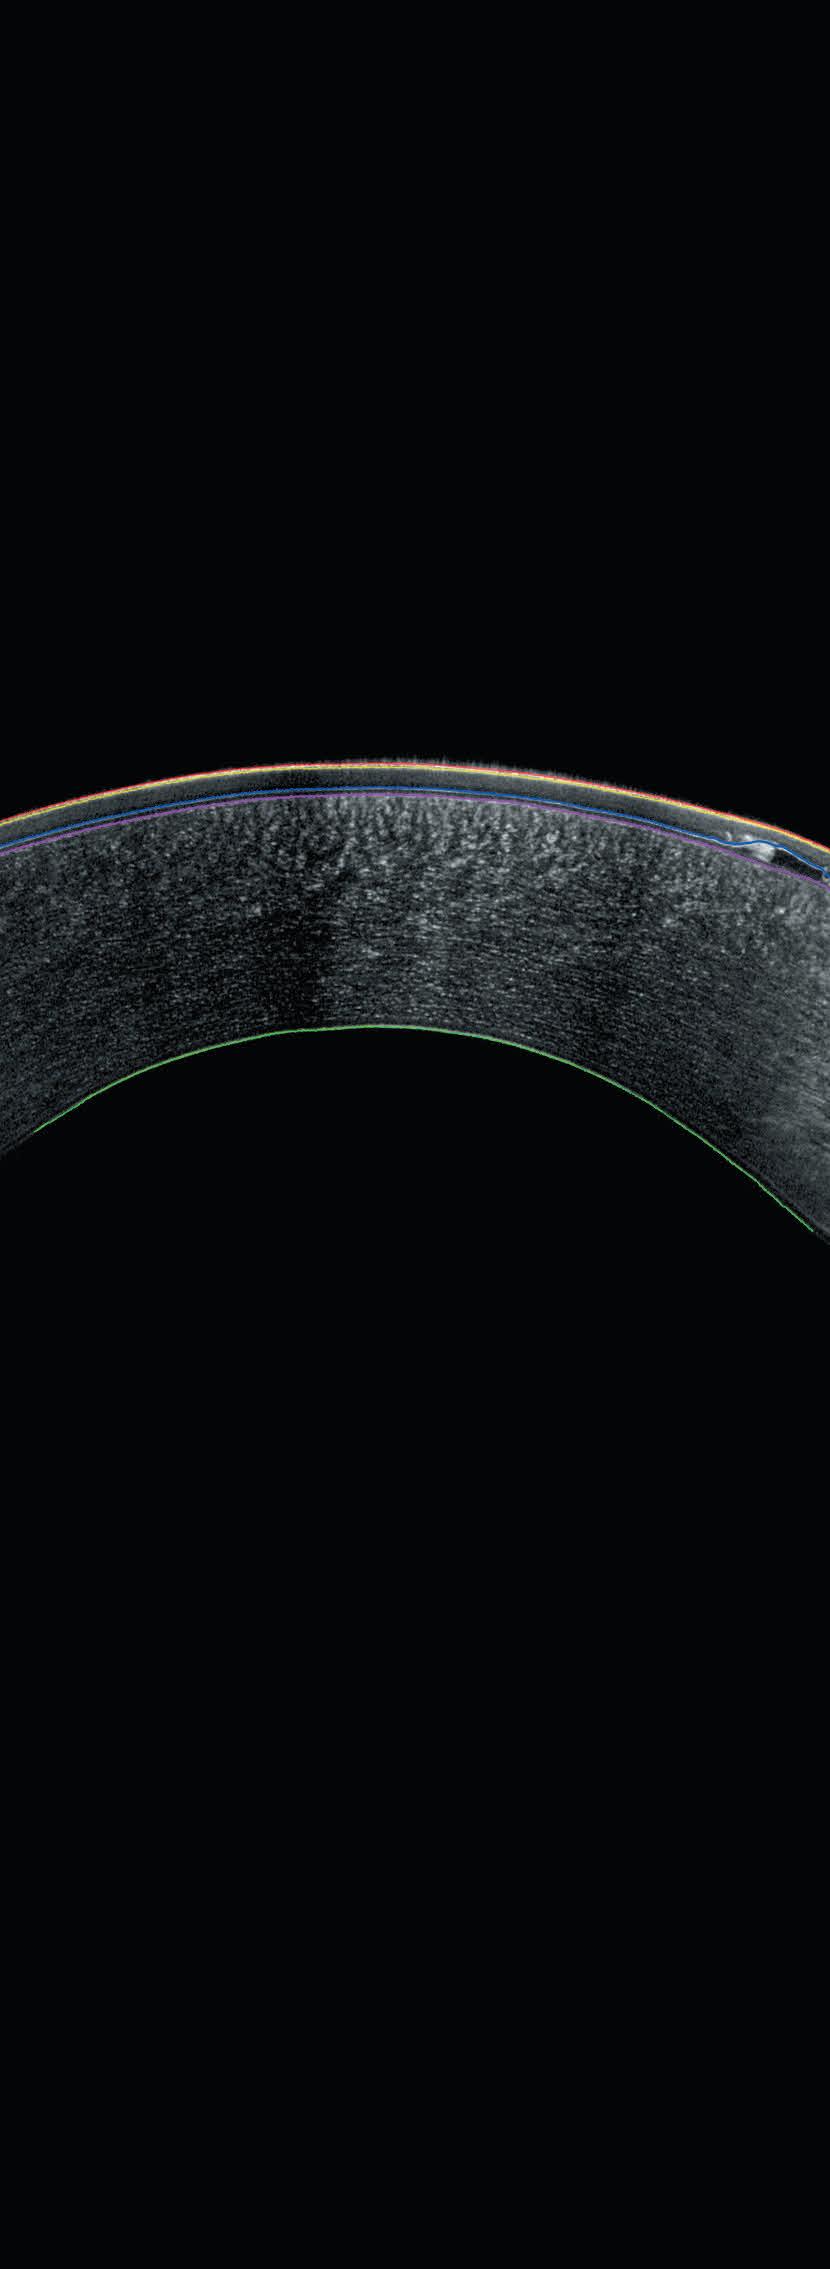

See the Unseen Experience Cornea Layer Segmentation

Detailed Sub-Layer Assessment

Combining the proven power of Scheimpflug imaging with the precision of ultra high-resolution OCT enables the detection of previously unseen corneal pathologies with unprecedented clarity.

Diagnose earlier. Treat smarter. Care deeper.